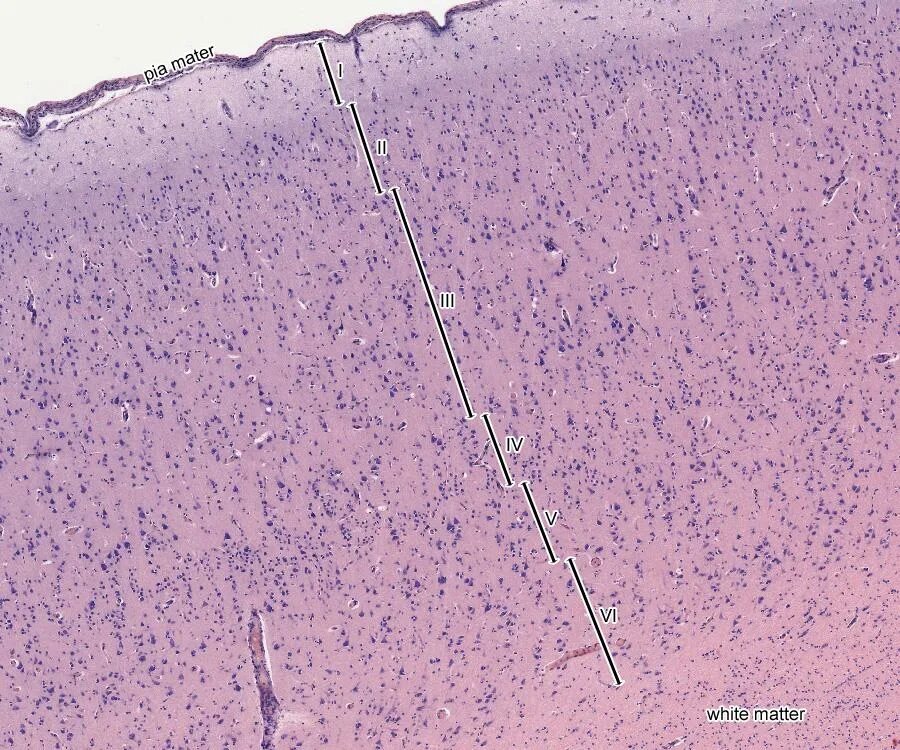

Гистологический срез это